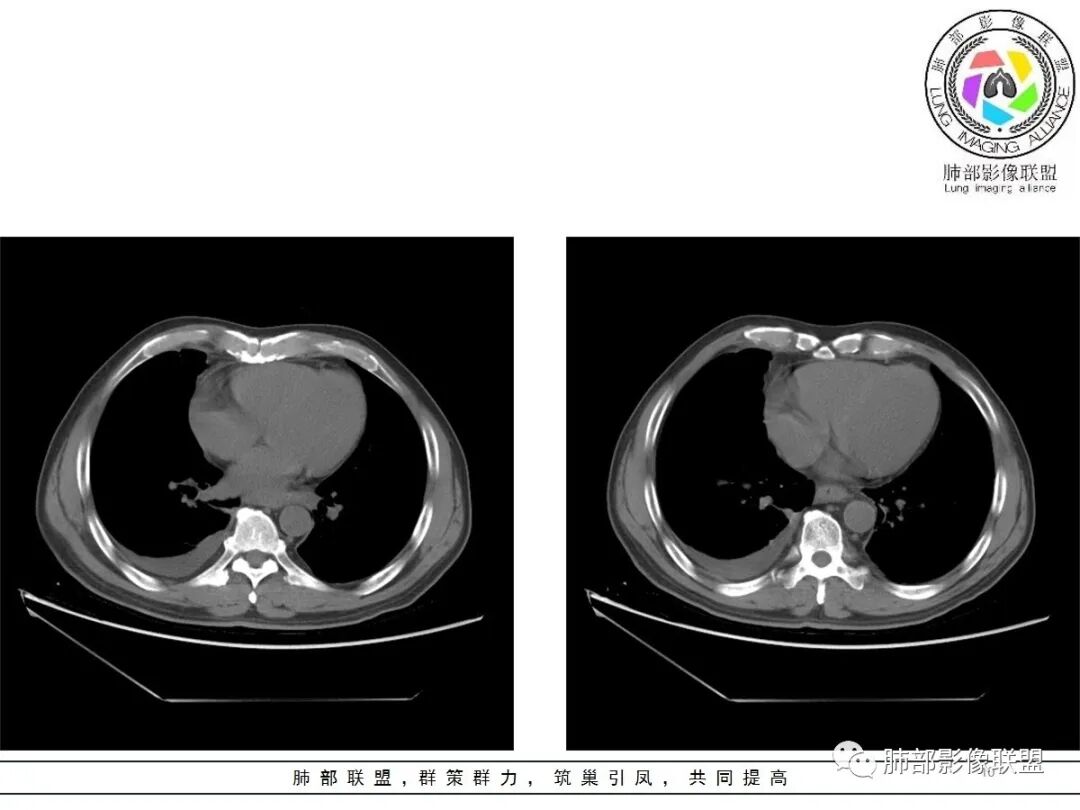

周围脂肪间隙密度增高,内部小点状很低密度影

右侧少量胸水

19日,4天后, 内部低密度影有,周围渗出增多,胸水增多

薄膜状强化

影像上周围病灶变化明显

常规肿瘤侵犯不支持,太快

应该是炎性病变渗出

脂肪密度明显,还有钙化、囊性病变,支持含脂质类病变破裂

周围是化学性炎症或出血所致

后期强化,可能与炎症有关

可能:1、肿瘤或瘤样病变破裂出血或内部物质外溢所致2、炎性病变所致

对比一下:

肿瘤样病变破裂所致纵隔炎应该没错

南边:肿瘤或肿瘤样病变破裂所致纵隔炎,这是大方向